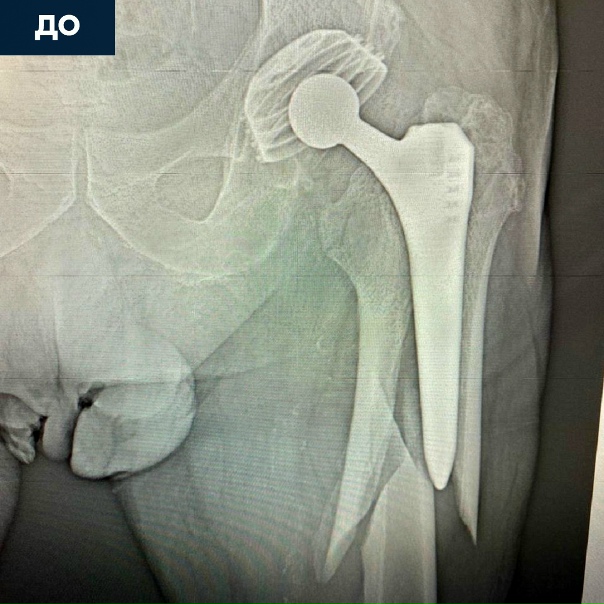

Перелом Тазобедренного Сустава: Диагностика и Лечение